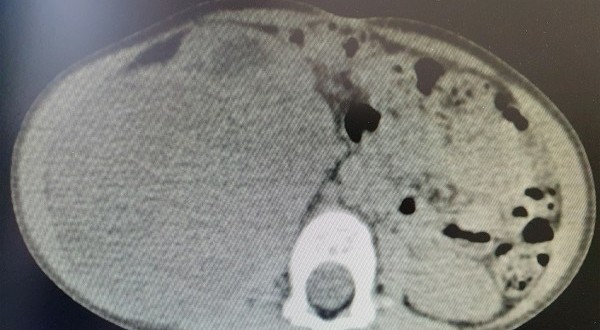

Shërbimi Spitalor Klinik dhe Universitar i Kosovës ka njoftuar se në Klinikën e Kirurgjisë së Fëmijëve të Qendrës Klinike Universitare të Kosovës, mjekët kirurgë, të asistuar nga ekipi i anestezionit, kanë operuar me sukses një fëmijë të moshës 2 vjeçare, duke ia larguar tumorin, i cili ia kishte përfshirë gjysmën e barkut.

“Operacioni u realizua, pas trajtimit dhe ekzaminimeve të vazhdueshme nga mjekët pediatër-onkologë. Pacienti është në gjendje të mirë shëndetësore dhe pritet të lirohet shumë shpejt për në shtëpi”, thuhet në njoftimin e SHSKUK-së.